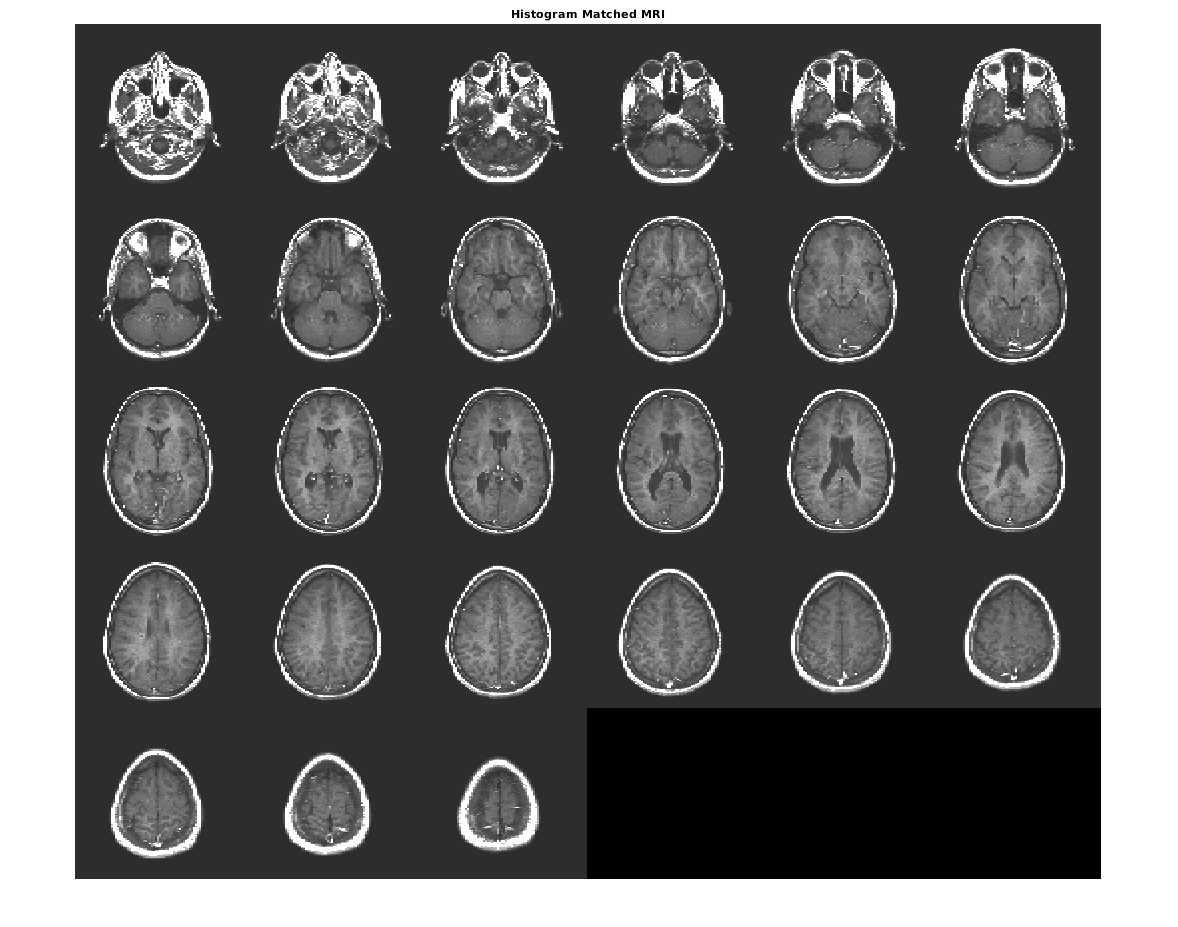

Совпадайте с гистограммой D к гистограмме полноразмерного ref.

Dmatched = imhistmatchn(D,ref);

Отобразите вывод. Заметьте, что уровни яркости выхода более тесно совпадают со ссылочным изображением, чем оригинальное изображение.

figure

montage(Dmatched,'DisplayRange',[])

title('Histogram Matched MRI')